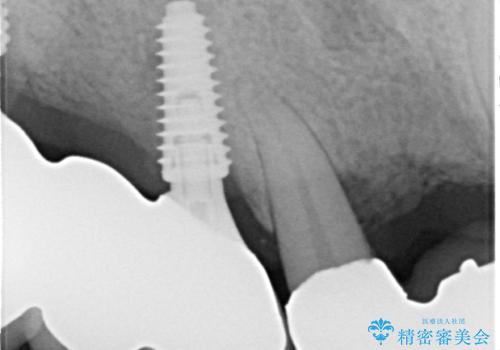

ブリッジの土台となっている歯は全て抜歯が必要な状態であったため、事前に仮歯を用意して、極力抜歯と同時にインプラントを埋入し、速やかに仮歯を装着して噛めるように処置を進めて行くこととしました。

手前の歯は骨の欠損が著しいため、抜歯後暫く待ってから埋入を行うこととしました。

後方2本を先に埋入し、即日で仮歯を装着しましたが、徐々にインプラントが骨内で緩んでしまい、手前のインプラント埋入時に再埋入することとなりました。

再埋入後は緩くなることもなく、無事に補綴治療を行うことができました。